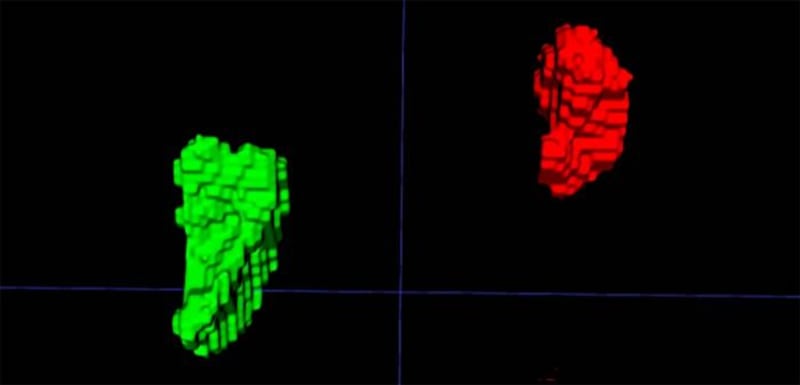

Y es que un equipo de investigadores liderado por la doctora Elena Ghotbi, del Johns Hopkins University School of Medicine, en Estados Unidos, entrenó un modelo de aprendizaje profundo para medir el volumen de las glándulas suprarrenales a partir de tomografías de tórax ya realizadas.

El indicador, llamado Índice de Volumen Suprarrenal (AVI, por sus siglas en inglés), se define como el volumen de las glándulas suprarrenales dividido por la estatura al cuadrado.

Hallaron que un AVI mayor se correlaciona con niveles más altos de cortisol, mayor carga alostática, estrés percibido elevado, y con un aumento en el riesgo futuro de insuficiencia cardiaca y mortalidad. Esto sugiere que AVI no solo refleja estrés crónico, sino que también puede predecir consecuencias graves para la salud.